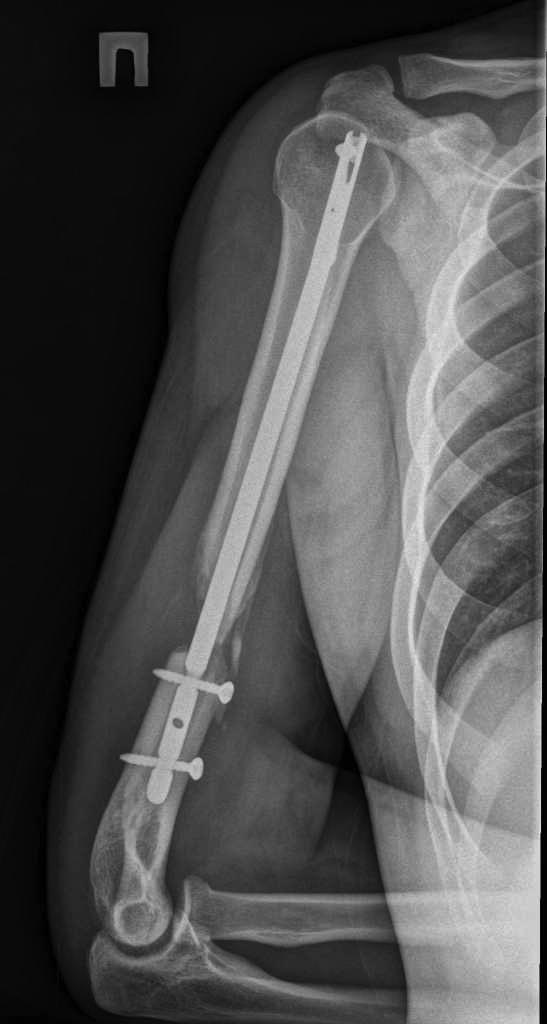

Здравствуйте уважаемые форумчане. Представляю Вашему вниманию очередной сломанный

штифт. Пациент 25 лет, в сентябре 2012 г ДТП. Кроме всего прочего, открытый перелом правого

плеча с дефектом костной ткани. При поступлении выполнено ПХО и ЧКО из 2 колец. После

заживления раны выполнен БИОС плеча. Штифт сОлидный, Остеомед. Пару дней назад во время

попытки открытия крышки банки (нагрузка по ротации) почувствовал боль в плече. Результат на

снимке. Планируем удалить оба отломка (дистальный открыто) и перештифтовать более

массивным штифтом. Вопрос 1: есть ли вариант в данном случае закрыто удалить дистальный

франгмент НЕканюлированного штифта. Особых инструментов для удаления сломаных штифтов не

имеем. Вопрос 2: как вариант рассматриваем выполнить ЧКО удалив предварительно только

проксимальный фрагмент штифта. СтОит ли? Вариант накостного остеосинтеза с пластикой и без

не рассматриваем. Спасибо за внимание.